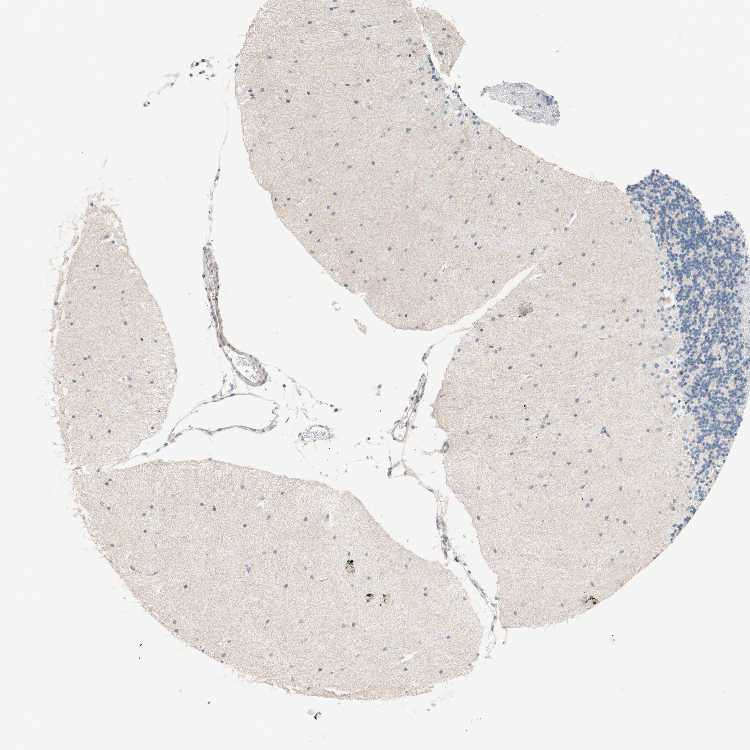

CEREBELLUM - Antibody stainingi

Antibody staining in the annotated cell types in the current human tissue is reported as not detected, low, medium, or high, based on conventional immunohistochemistry profiling in selected tissues. This score is based on the combination of the staining intensity and fraction of stained cells.

Each image is clickable and will lead to virtual microscopy that enables deeper exploration of all samples and also displays staining intensity scores, fraction scores and subcellular localization as well as patient and tissue information for each sample.

Antibody HPA008996Antibody HPA009413Antibody CAB013461

Purkinje cells LowNot detectedNot detected

Cells in granular layer Not detectedNot detectedMedium

Cells in molecular layer Not detectedNot detectedNot detected